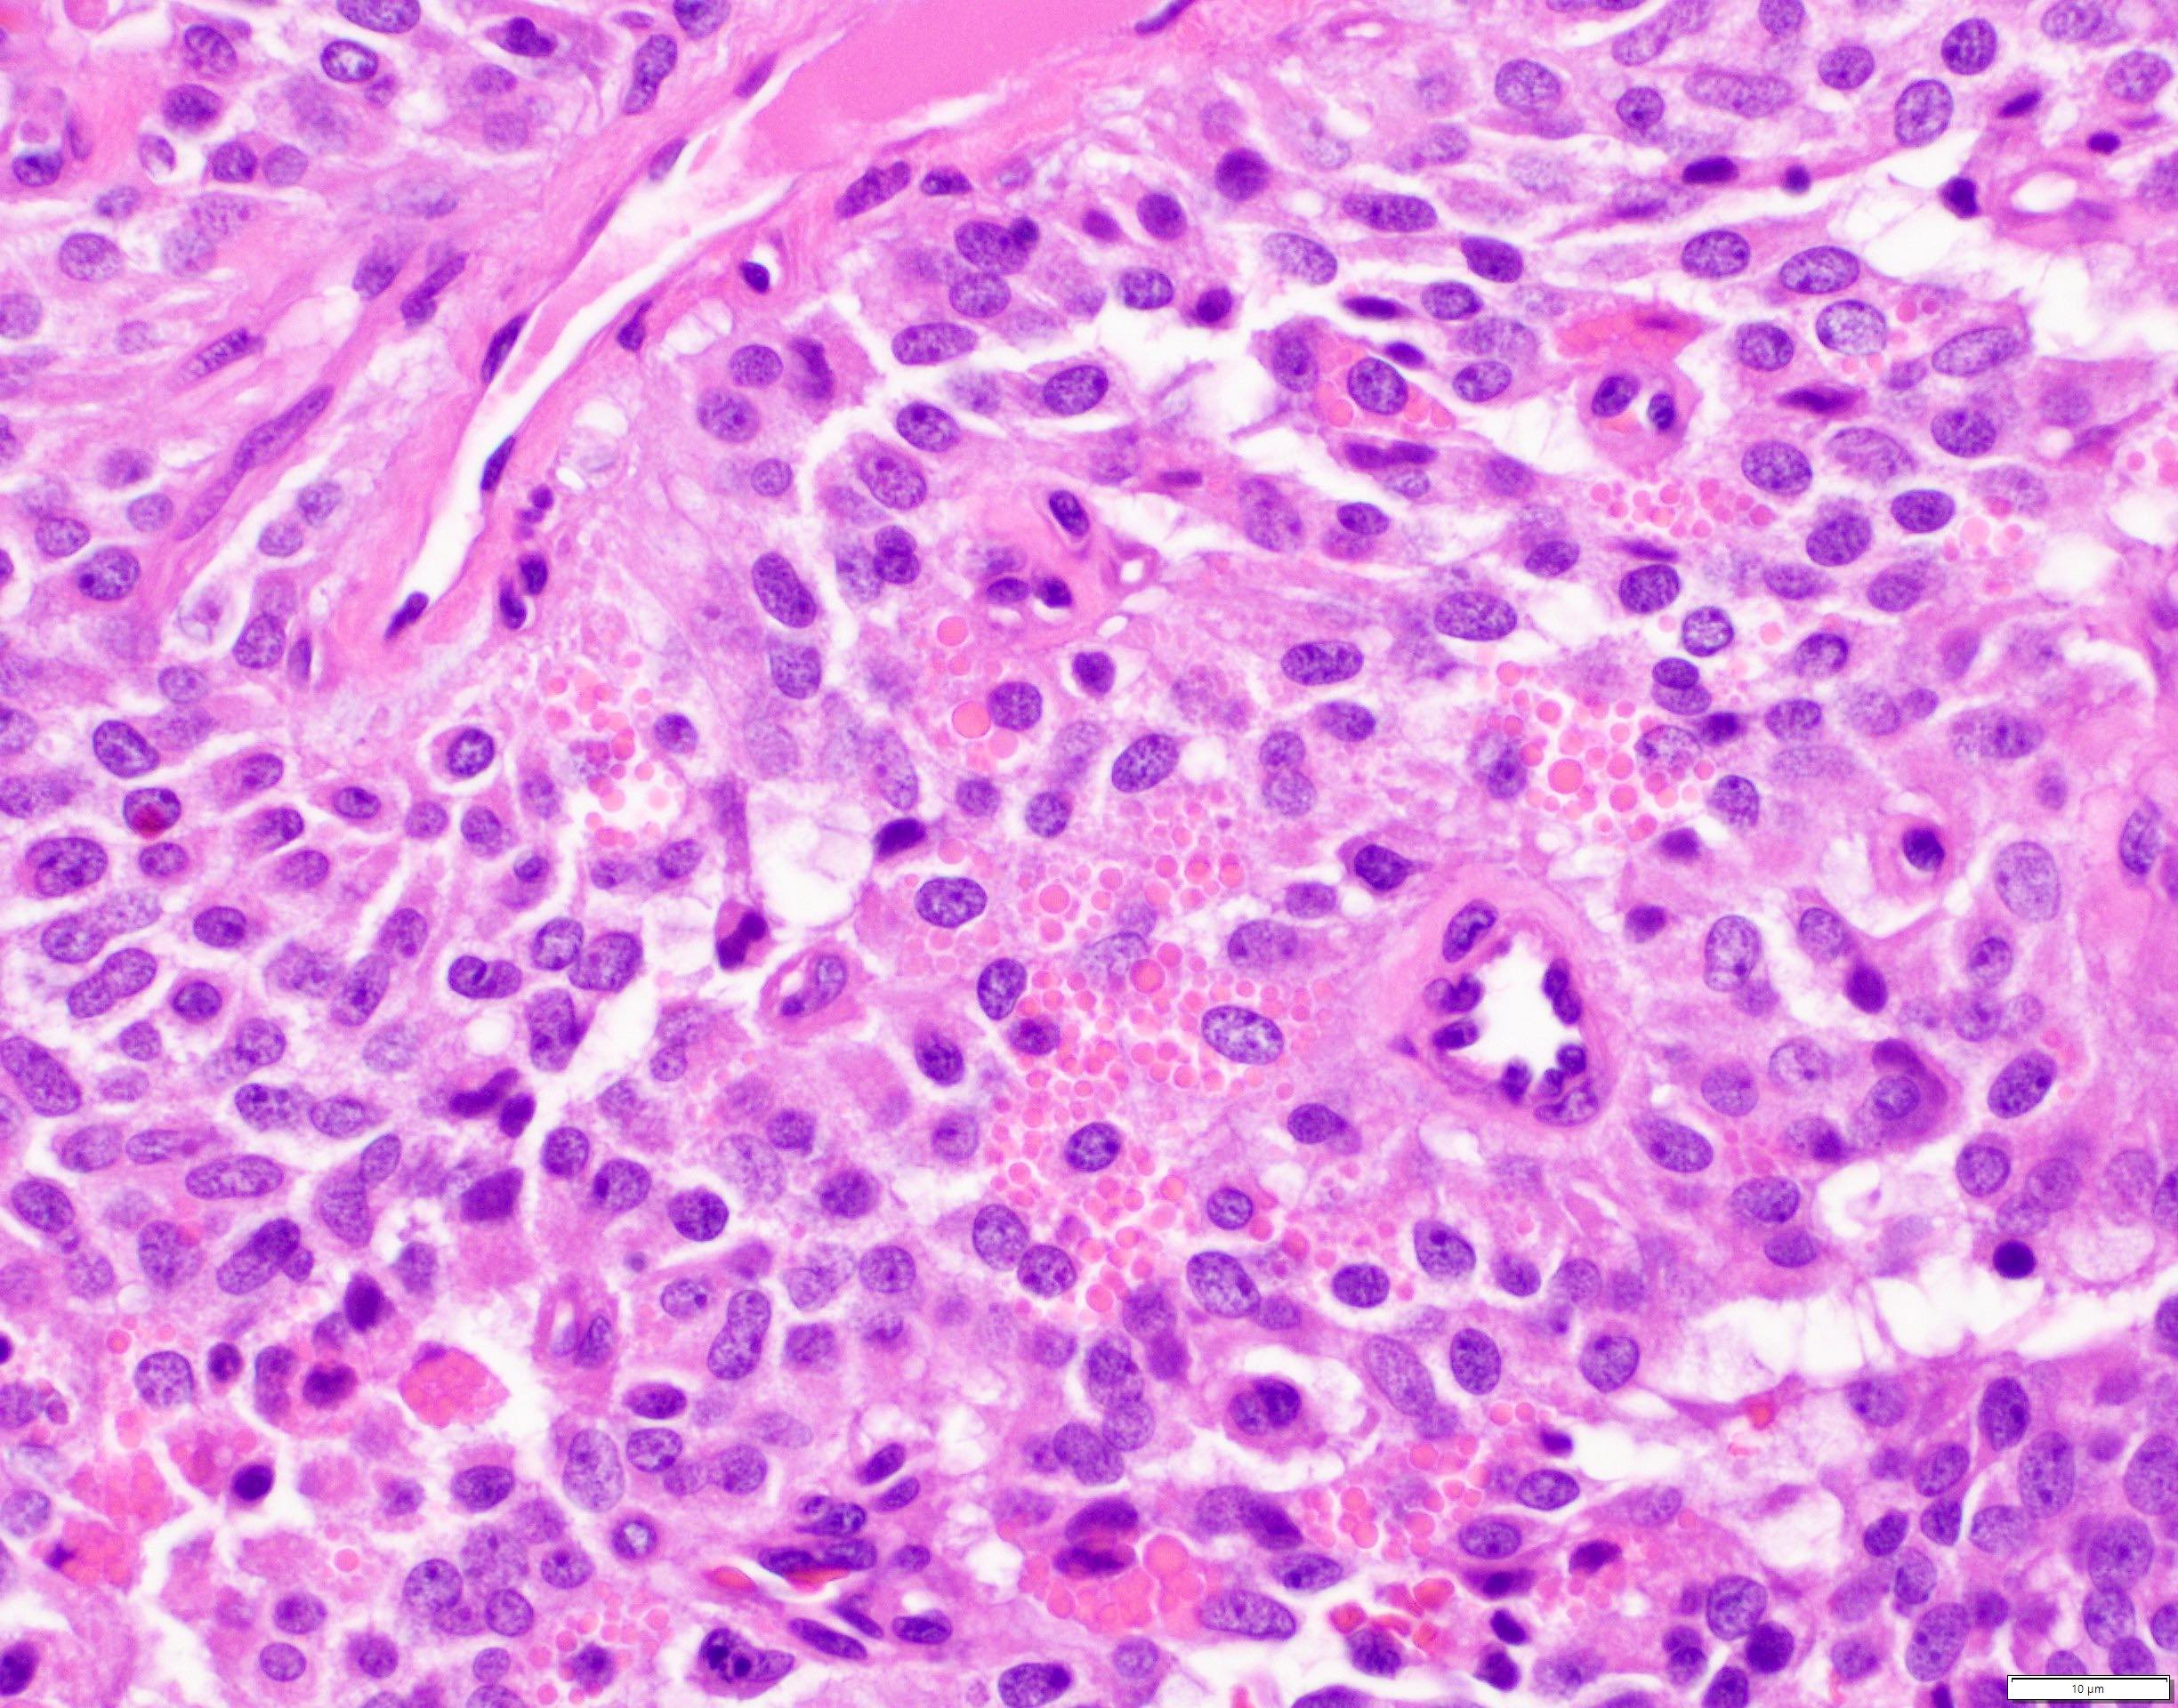

Microscopic (histologic) description

- Tumors are heterogeneous, with variable admixture of solid and pseudopapillary areas

- Solid areas are comprised of uniform cells admixed with capillary sized blood vessels

- Pseudopapillae are formed due to tumor cells getting detached from blood vessels forming fibrovascular stalks or rosette-like structures (Arch Pathol Lab Med 2020;144:829)

- Stroma usually shows various degrees of hyalinization or evidence of degeneration, such as hemorrhage, foamy macrophages, calcification and cholesterol clefts

- Tumor cells usually have a moderate amount of eosinophilic cytoplasm with intracytoplasmic hyaline globules (PAS+ and diastase resistant, positive for alpha-1-antitrypsin) and perinuclear vacuoles (Am J Surg Pathol 2011;35:981)

- Relatively uniform nuclei with finely textured chromatin, inconspicuous nucleoli and characteristic longitudinal grooves

- Variants include clear cell, oncocytic and pleomorphic

- Rare mitotic figures

- Although grossly well circumscribed, microscopic finding of infiltration to the surrounding pancreatic tissue is not uncommon

- Rare cases of highly aggressive behavior; histological features in those cases included diffuse growth pattern, extensive necrosis, significant nuclear atypia, high mitotic count (35 - 70/50 high power fields) or sarcomatoid features (Am J Surg Pathol 2005;29:512)

Microscopic (histologic) images

Contributed by Monika Vyas, M.D., Omid Savari, M.D. and Raul S. Gonzalez, M.D.